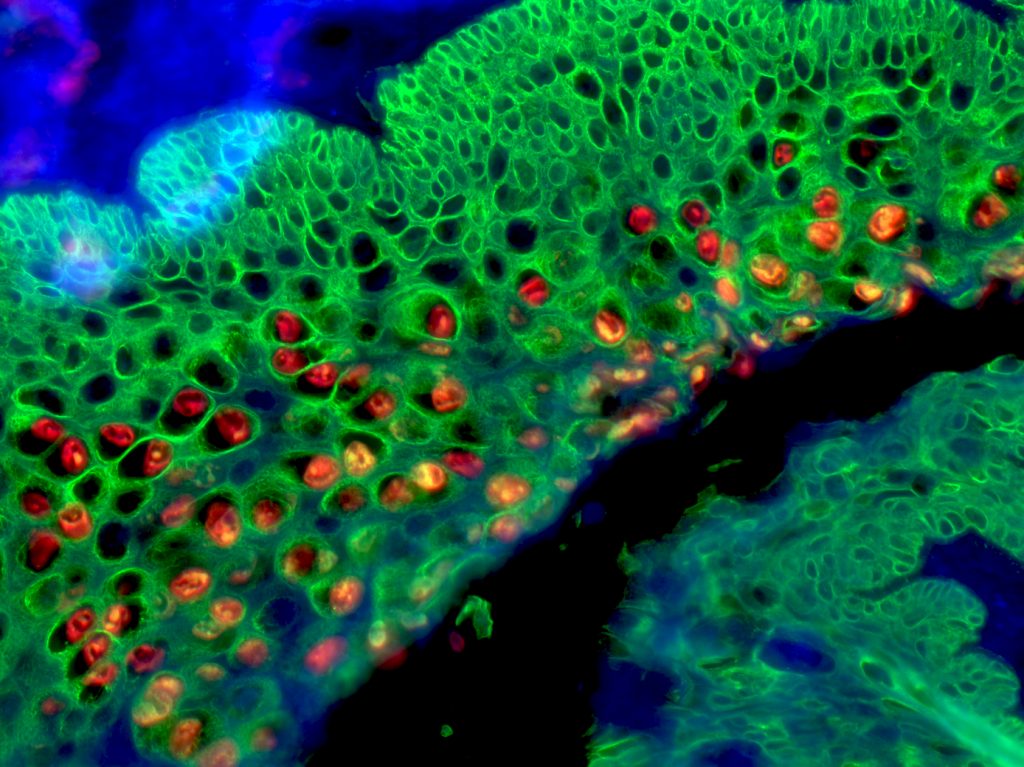

Runner Up:

Dual L1/K14 Immunofluorescence in MmuPV1-infected Mouse Cervical Epithelium by Laura Gunder and Evie Carchman

This is a section of fixed tissue from an immunocompromised NOD SCID gamma mouse infected with mouse papillomavirus (MmuPV1) in the cervicovaginal canal. Dual L1/K14 tyramide signal amplification (TSA) immunofluorescence was performed: L1 stained red and Keratin14 stained in green. The image was taken using a Zeiss Axio Imager M2 imaging system. This stain allows for visualization of productive virus in tissue.